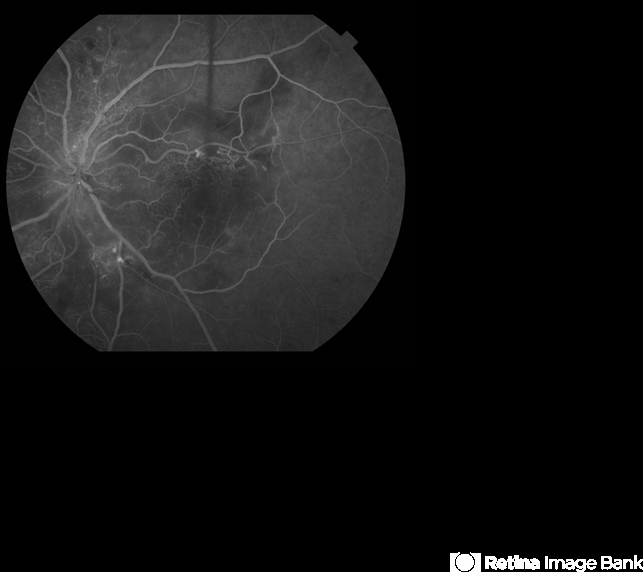

The capillary changes around the FAZ and also superior,inferior and nasal to disc in addition to the vascular changes on the disc surface may be suggestive of a previous vein occlusion.

- hypertensive retinopathy, papilledema, ischemia

- A 35-year-old man has headaches and decreased vision. The right eye measures 20/25 and the left eye measures 3/200. The blood pressure measures 180/110.This fluorescein angiogram shows leakage of dye from the optic disc (papilledema), ischemia, and dilated capillaries around the foveal avascular zone